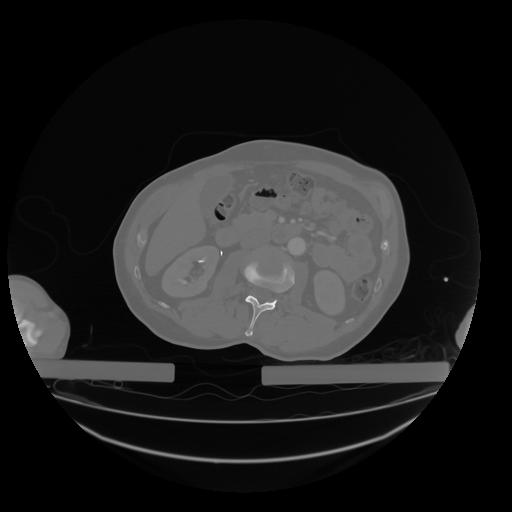

28 CUERPO,CE,Vol,2.0,CUERPO,,